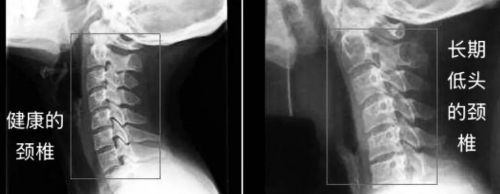

工作压力大,睡前刷手机,碎片化娱乐越来越普遍,加上对床垫枕头的错误选择都是导致睡眠问题的原因,让颈椎曲线慢慢产生变化,导致更严重的问题。

颈椎病已经不是老年人的”专利“了,中青年人已跻身颈椎病大军。这与智能手机的普及以及移动互联的迅猛发展密切相关,地铁里、公交上、餐桌边,甚至在马路上,随处可见低头刷手机的人。

数据显示30岁以下的颈椎病患者占接近40%。颈椎病的低龄化已演变成一种趋势,并以不可思议的速度增加中。人们1/3的时间都在睡眠,不适当用枕也可能导致颈椎问题加剧。